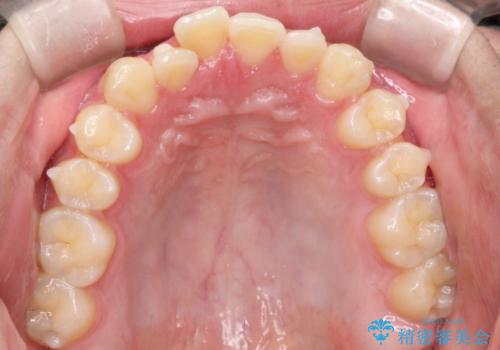

初診時の歯並びの状態としては、上下ともに前歯部の中等度以上のがたつき(叢生)があり、右の前歯が1本飛び出した状態でした。

抜歯は行わず上下顎ともに、主に歯列弓の拡大とディスキング(歯と歯の間に隙間を作る処置)を行い叢生を改善しました。